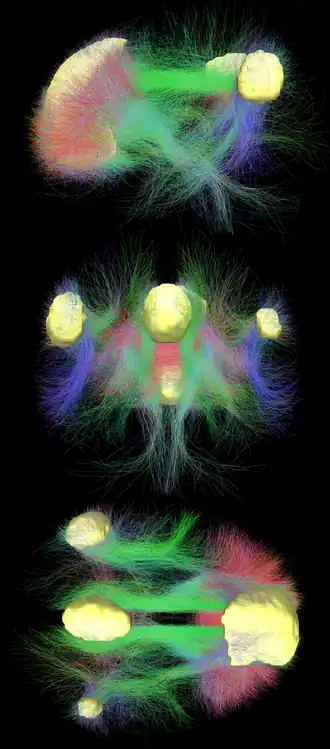

La red neuronal por defecto (RND) es un conjunto de regiones del cerebro que colaboran entre sí y que podría ser responsable de gran parte de la actividad desarrollada mientras la mente está en reposo.

La RND demuestra que el cerebro no se encuentra al ralentí cuando no interviene en actividades conscientes (por ejemplo, cuando se está bajo los efectos de una anestesia). Probablemente, emite señales de sincronización para coordinar la actividad entre esas regiones, lo que aseguraría que las mismas se hallen listas para reaccionar de forma concertada ante los estímulos.

Cabe la posibilidad de que la RND organice el modo en que el cerebro organiza los recuerdos y diversos sistemas que necesitan cierta preparación ante futuros sucesos. Por lo demás, si la RND prepara al cerebro para la actividad consciente, las investigaciones sobre su comportamiento pueden revelar las claves para comprender la naturaleza de la experiencia consciente. Igualmente, las alteraciones de la RND podrían ser la causa subyacente de errores mentales, tanto los más sencillos como los más complejos, desde la enfermedad de Alzheimer a la depresión.